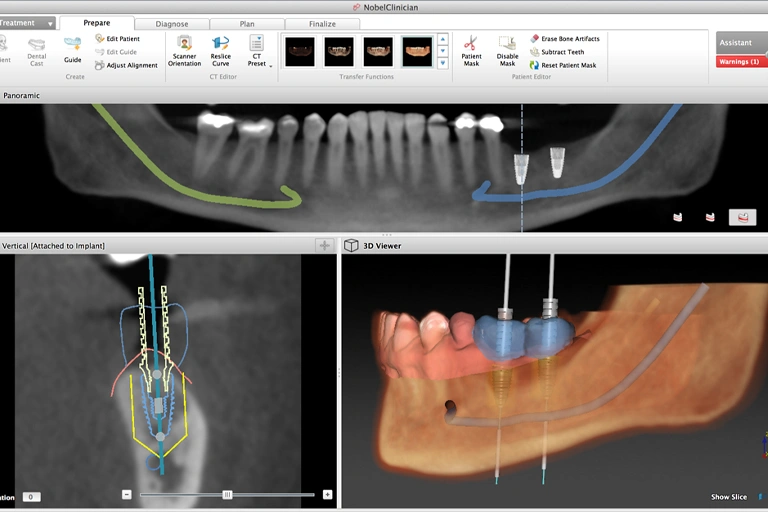

A Cone Beam CT scan (CBCT scan) is taken to show your jaw in 3 dimensions. Together, we will evaluate the condition of your jaws, the quantity and quality of your available bone, as well as your sinus’ and location of your nerves. Using the CT Scan data Dr. Oestervemb can then accurately plan the position of each dental implant before fabricating the surgical guide.